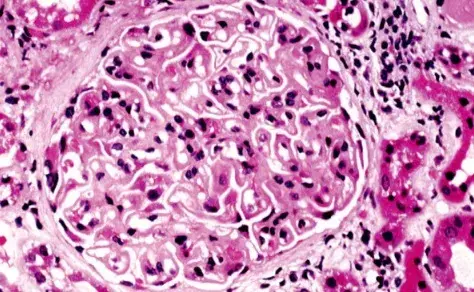

nefrite lupica